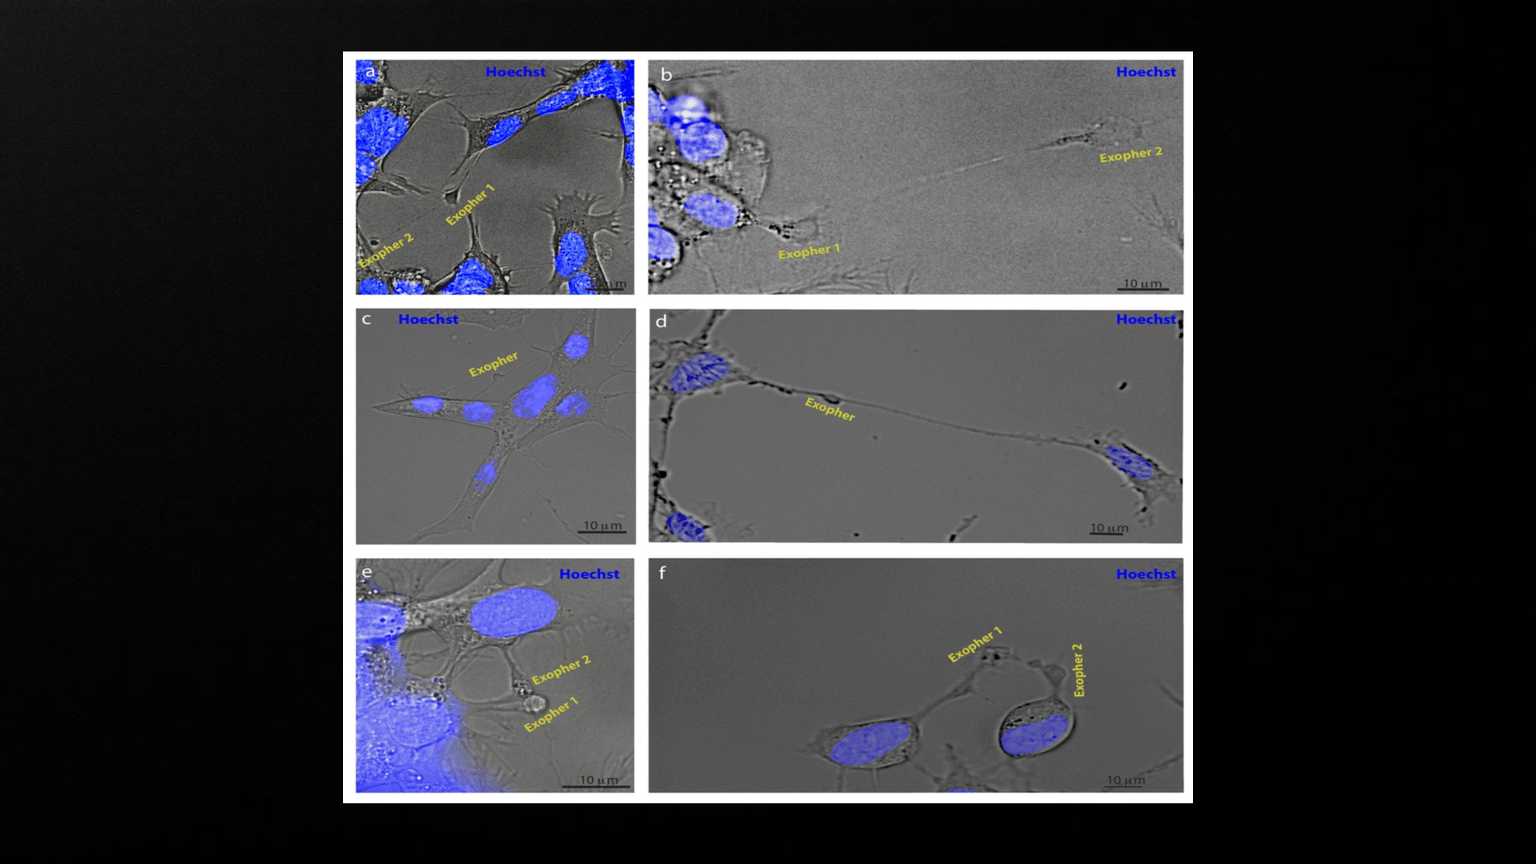

<p>Exophers appear to mediate neuronal communication. SH-SY5Y cells were stained with Hoechst and imaged using brightfield and fluorescence microscopy. a, b) Examples of exophers emanating from another exopher (N = 4 observations). c, d) Examples of exophers connected to two or more different cells via nanotubes (N = 6). e, f) Examples of exophers originating in two adjacent cells in contact with each other (N = 3).</p>

Exophers appear to mediate neuronal communication. SH-SY5Y cells were stained with Hoechst and imaged using brightfield and fluorescence microscopy. a, b) Examples of exophers emanating from another exopher (N = 4 observations). c, d) Examples of exophers connected to two or more different cells via nanotubes (N = 6). e, f) Examples of exophers originating in two adjacent cells in contact with each other (N = 3).